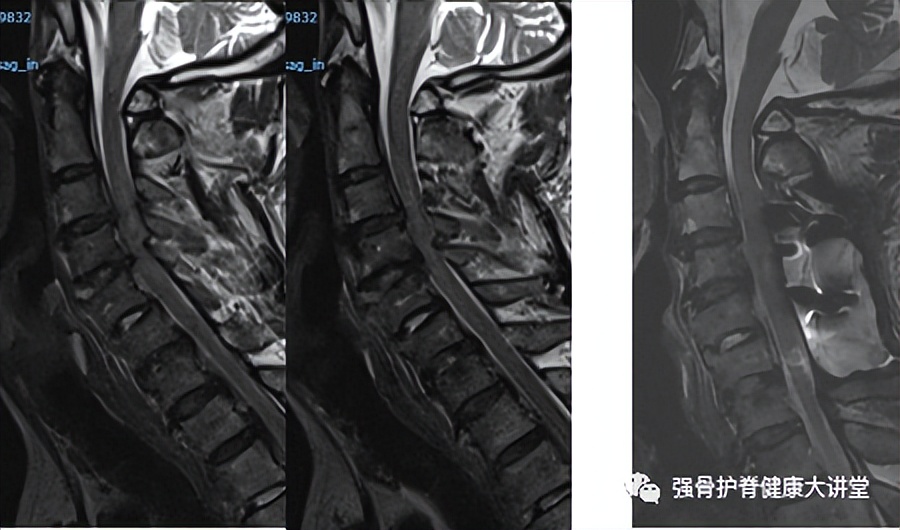

下面分享我院治疗的76岁老年男性,因头晕摔倒后出现颈椎骨折,患者入院时四肢肌力1-2级,大小便*禁失**;手术后1月四肢肌力恢复至3-4级,小便正常,大便稍无力。

左侧为术前MR,右侧为术后MR,手术后C3-C6节段椎管得到充分减压。

强直性脊柱炎患者因外伤后致颈椎骨折,出现严重的脊髓损伤,此时手术治疗无疑是脊髓神经减压、恢复颈椎稳定性的首选方案。一经发现,应尽早排除内科禁忌症,尽快挽救神经功能,避免相关并发症的发生。